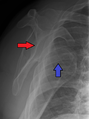

خلع سفلي للذراع بعد حادث سيارة. لاحظ كيفية بروز عظمة العضد. كما يظهر أيضاً كسر في الحدبة الكبرى.

الخلع السفلي هو النوع الأقل شيوعاً، ويحدث في أقل من 1% من الحالات. تسمى هذه الحالة بالخلع المنتصب لأن المصاب غالباً ما يظهر ممسكاً بذراعه إلى الأمام أو إلى أعلى الرأس.[14] يحدث الخلع السفلي بسبب جذب الذراع بقوة مما يجبر عظمة العضد على الخروج من الأخرم.[15] تصاحب هذه الحالة أضرار بالغة في الأعصاب، الأوعية الدموية، أوتار العضلات، الأربطة حسب آلية الاصابة.